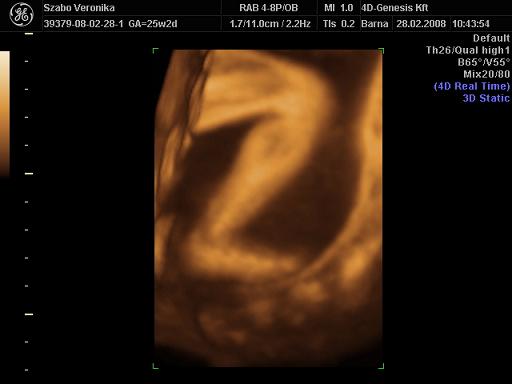

A doki szerint pufók kislány

És egy tappancs 2008.03.08 19:45